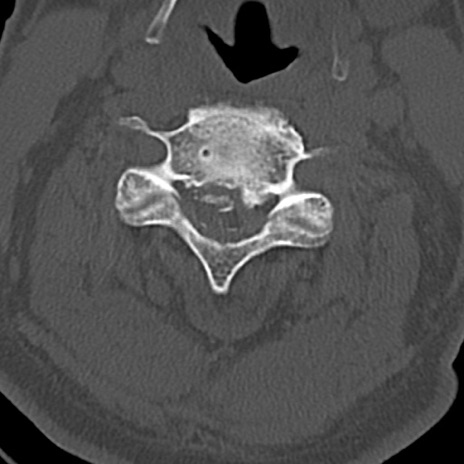

頚椎CT

横断像